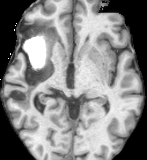

Figure 4: Qualitative comparisons on healthy anatomy reconstruction between UNA and state-of-the-art modality-agnostic synthesis models. Testing images are from real stroke datasets (ISLES [22] and ATLAS [36]), where the stroke lesion annotations are provided, yet the ground truth healthy anatomy is unavailable. The last row shows a failure case of UNA, where it “over-corrects” the diseased anatomy. Pathology regions are circled in red.

As shown in Fig. 4, other models tend to generate unrealistic patterns within and around abnormalities, whereas UNA’s reconstructions are notably more visually coherent. Additionally, we present a failure case (4thth{}^{\text{th}}start_FLOATSUPERSCRIPT th end_FLOATSUPERSCRIPT row in Fig. 4), where we observe that UNA tends to “over-distinguish” the reconstructed healthy anatomy from the diseased regions, particularly in challenging scenarios where the pathology pattern completely occludes the underlying anatomy.